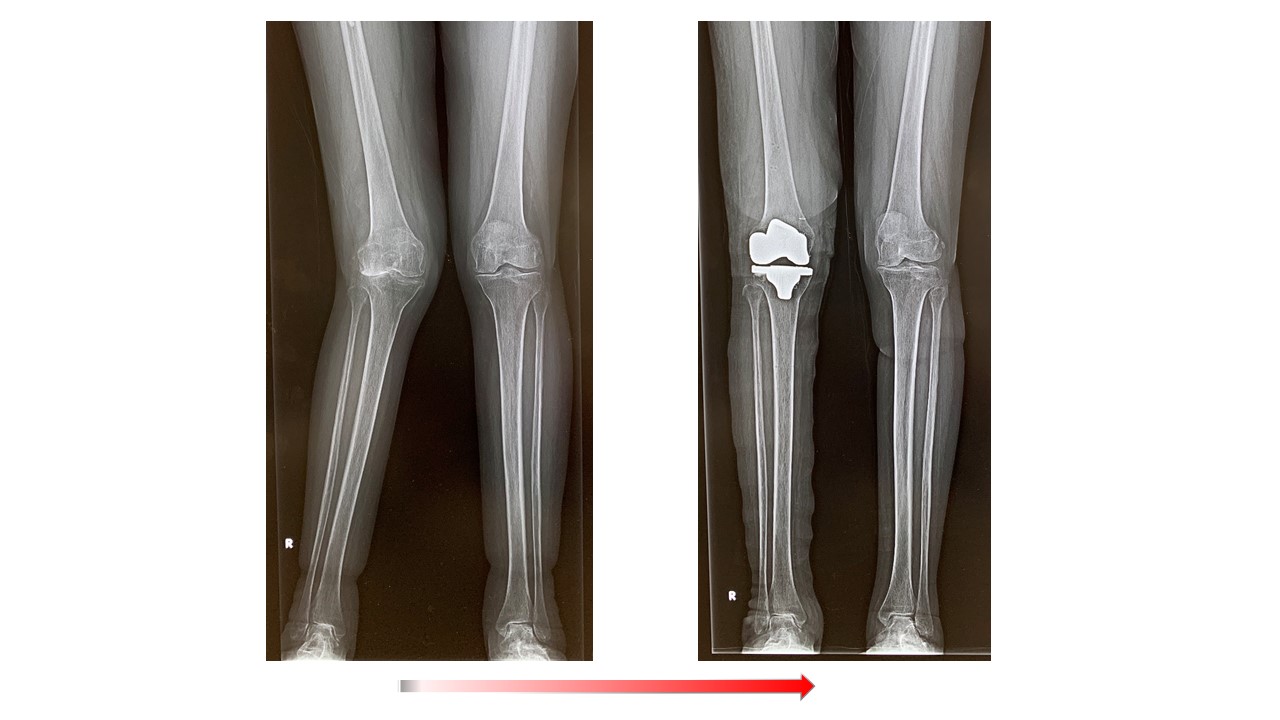

人工膝関節全置換術(Total knee arthroplasty、TKA)ではナビゲーションシステムを使用して手術を行っています。より良い術後の満足度を得るため、生理的な膝のバランス、アライメントなどを考慮に入れた上で、術中の膝の状態をみながら、最適なインプラントの設置位置を決めて手術を行っています。そのため以前に比べてより使い易く違和感の少ない人工膝の再現が可能になっています。これらの術前検査として、立位での下肢全長のレントゲン検査やMRI検査、骨密度検査等も行いながら、最適なインプラントの選択を行います。さらに長期的には良好な骨の状態を保つことが重要ですので、術後も骨粗鬆症薬等につき外来でフォローアップ致します。紹介受診の場合はかかりつけのクリニックで骨粗鬆症薬の投薬を継続頂いてます。